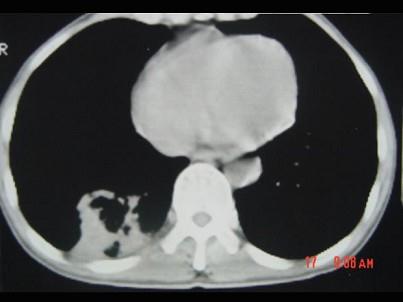

问题 男,40岁,胸背疼痛一周,消瘦一月,CT检查如图,最可能的诊断为 ( )

选项 A、右下肺肺泡癌 B、右下肺炎性假瘤 C、右下肺脓肿 D、右下肺炎 E、右下肺结核

答案 A